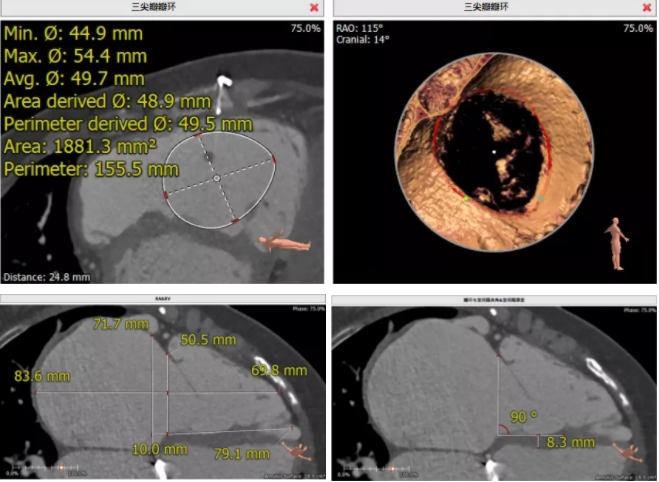

患者為68歲女性,14年前因“反復(fù)感冒、氣促”,檢查發(fā)現(xiàn)心臟瓣膜病,接受了“二尖瓣機(jī)械瓣置換術(shù)”。約5年前出現(xiàn)雙下肢水腫,活動(dòng)后心累氣緊,心臟彩超提示:三尖瓣返流。近年來三尖瓣返流逐漸加重并伴有輕微黃疸、雙下肢水腫,雖長(zhǎng)期服用利尿劑治療,但效果欠佳。郭惠明教授團(tuán)隊(duì)結(jié)合病史、超聲及CT評(píng)估,考慮患者瓣膜置換術(shù)后,三尖瓣重度返流,再次開胸行體外循環(huán)手術(shù)風(fēng)險(xiǎn)高,經(jīng)團(tuán)隊(duì)整體評(píng)估,決定采用最適合患者的LuX-Valve三尖瓣置換系統(tǒng)行微創(chuàng)治療,根據(jù)測(cè)量結(jié)果選擇植入JS/TTVI-28-55型號(hào)的LuX-Valve瓣膜。